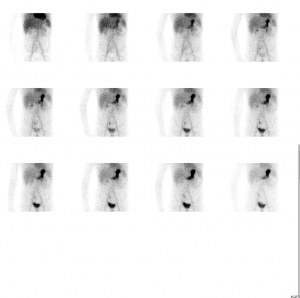

Images dynamiques : captation rapide et physiologique du traceur par la muqueuse gastrique.

Apparition synchrone d’une hyperfixation focale sous-ombilicale droite évoquant une cinétique de captation gastrique.